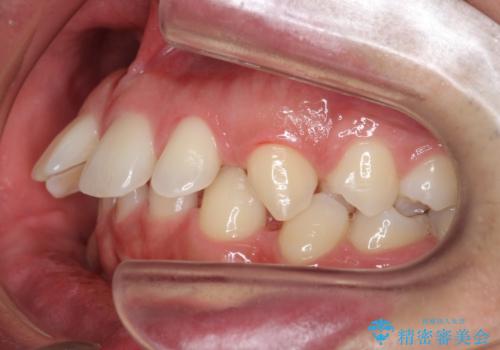

上はインビザラインで目立たないように前歯を下げ、下は難しいため、ワイヤー矯正で咬み込んでいる下の歯を沈める処置を初め行いました。最終的には上下ともインビザライン矯正で仕上げました。

下の前歯が生まれつき1本少なかったため、その部分には最終的にインプラントを入れ、下の歯が下がりすぎないようにかつ上の前歯にしっかり咬むように仕上げました。

今回は、時間はかかりましたが矯正治療で隙間を閉じ、天然の歯を保存することができました。セラミックで無理に一時的にかぶせるとその後大変な人生になるのが予想されます。

難ケースのため、患者様とともに根気強く治療に取り組んだ結果、しっかり治療することができました。